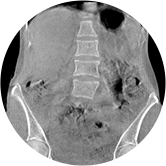

腰椎

髋关节